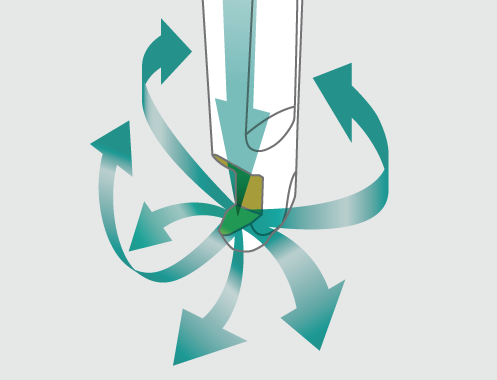

Oceania

NSK’s analysis of fluid dynamics gained through years of experience in developing turbine technology fully takes into account how a clinician must maneuver in the limited space inside the pocket.